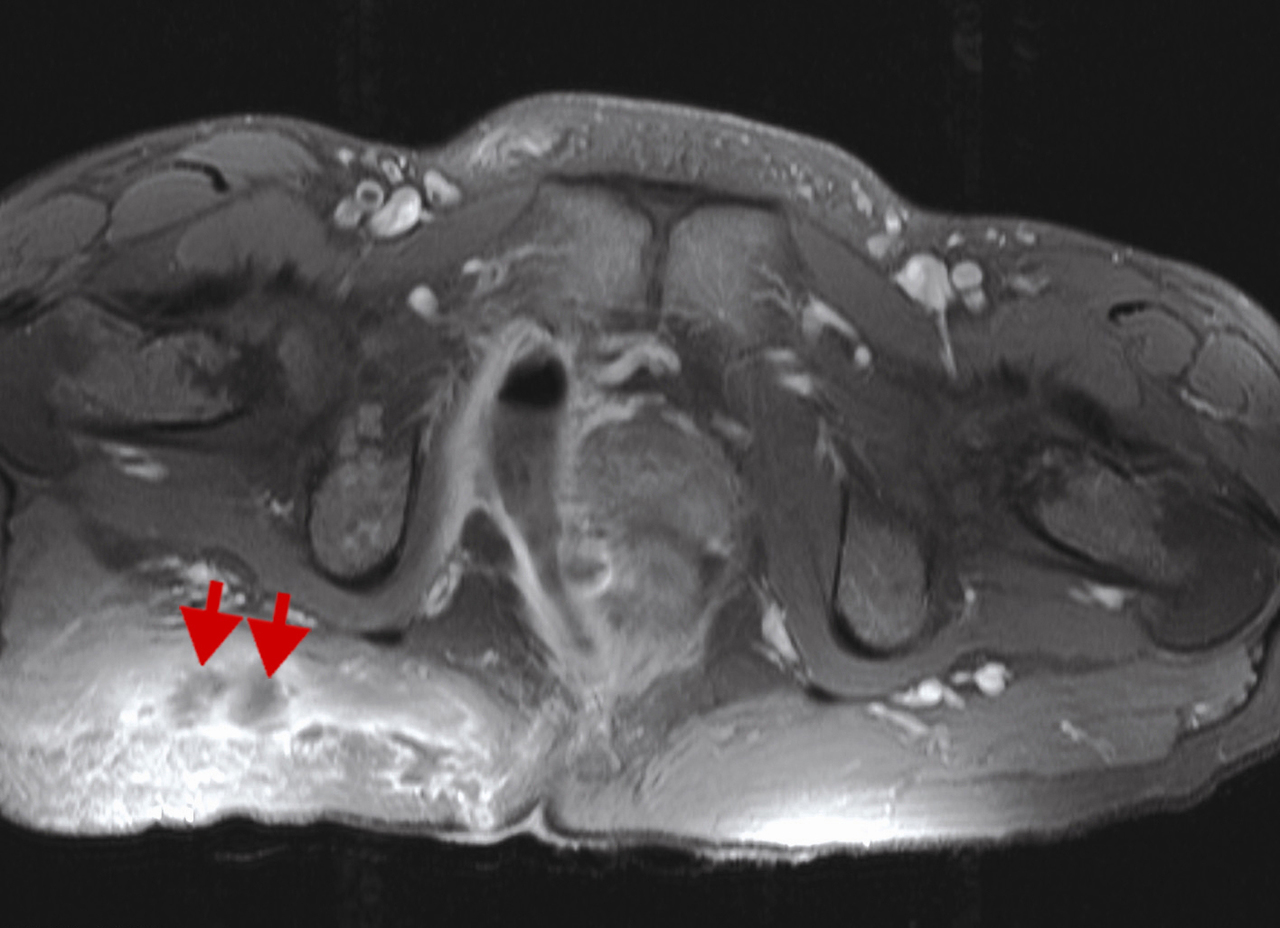

Atteine périnéale sévère avec trajets fistuleux multiples (flèches rouges) au niveau fessier. IRM en séquence T1 avec injection de gadolinium et saturation de graisses.